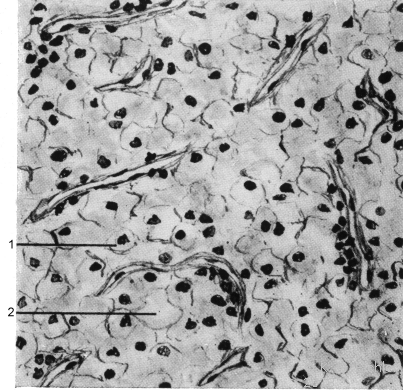

Hierbei sind die Tumorzellen in papillärer Struktur angeordnet (Abbildung 3).